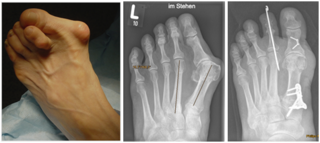

Begradigung durch Knochenverschiebung

Hierbei wird der Mittelfußknochen nach außen verschoben und mit zwei kleinen Schräubchen wieder befestigt (Osteotomie nach Chevron). Ebenfalls wird ein verkürzter Muskel gelöst, damit der Zeh in gerader Position verbleibt (sog. laterales Release). Sollte die Fehlstellung auch innerhalb der Zehe vorliegen, wird auch ein kleiner Keil am Großzehengrundglied entnommen (Osteotomie nach Akin).

Begradigung durch Stabilisierung

Bei fortgeschrittener Fehlstellung kommt es zu einer Instabilität des sog. TMT 1 Gelenkes, welches die Belastbarkeit der großen Zehe beim Gehen erschwert. Daher erfolgt eine Stabilisierung in diesem Bereich (Arthrodese des TMT I Gelenkes). Der Zeh wird hierbei durch die Entnahme eines kleinen Knochenkeils begradigt. Auch hier wird ein verkürzter Muskel gelöst, um die Stellung des Zehs langfristig zu sichern. Meist wird diese OP-Methode mit einer Osteotomie nach Akin kombiniert (s.o.).

Durch die Fehlstellung der Großzehe (Hallux valgus) ist es zur Ausbildung einer Krallenzeh gekommen. Die Korrektur ist in manchen Fällen nur möglich, wenn beide Zehen begradigt werden. Im rechten Bild ist noch der Draht zu erkennen, der vier Wochen nach der Operation entfernt wird.